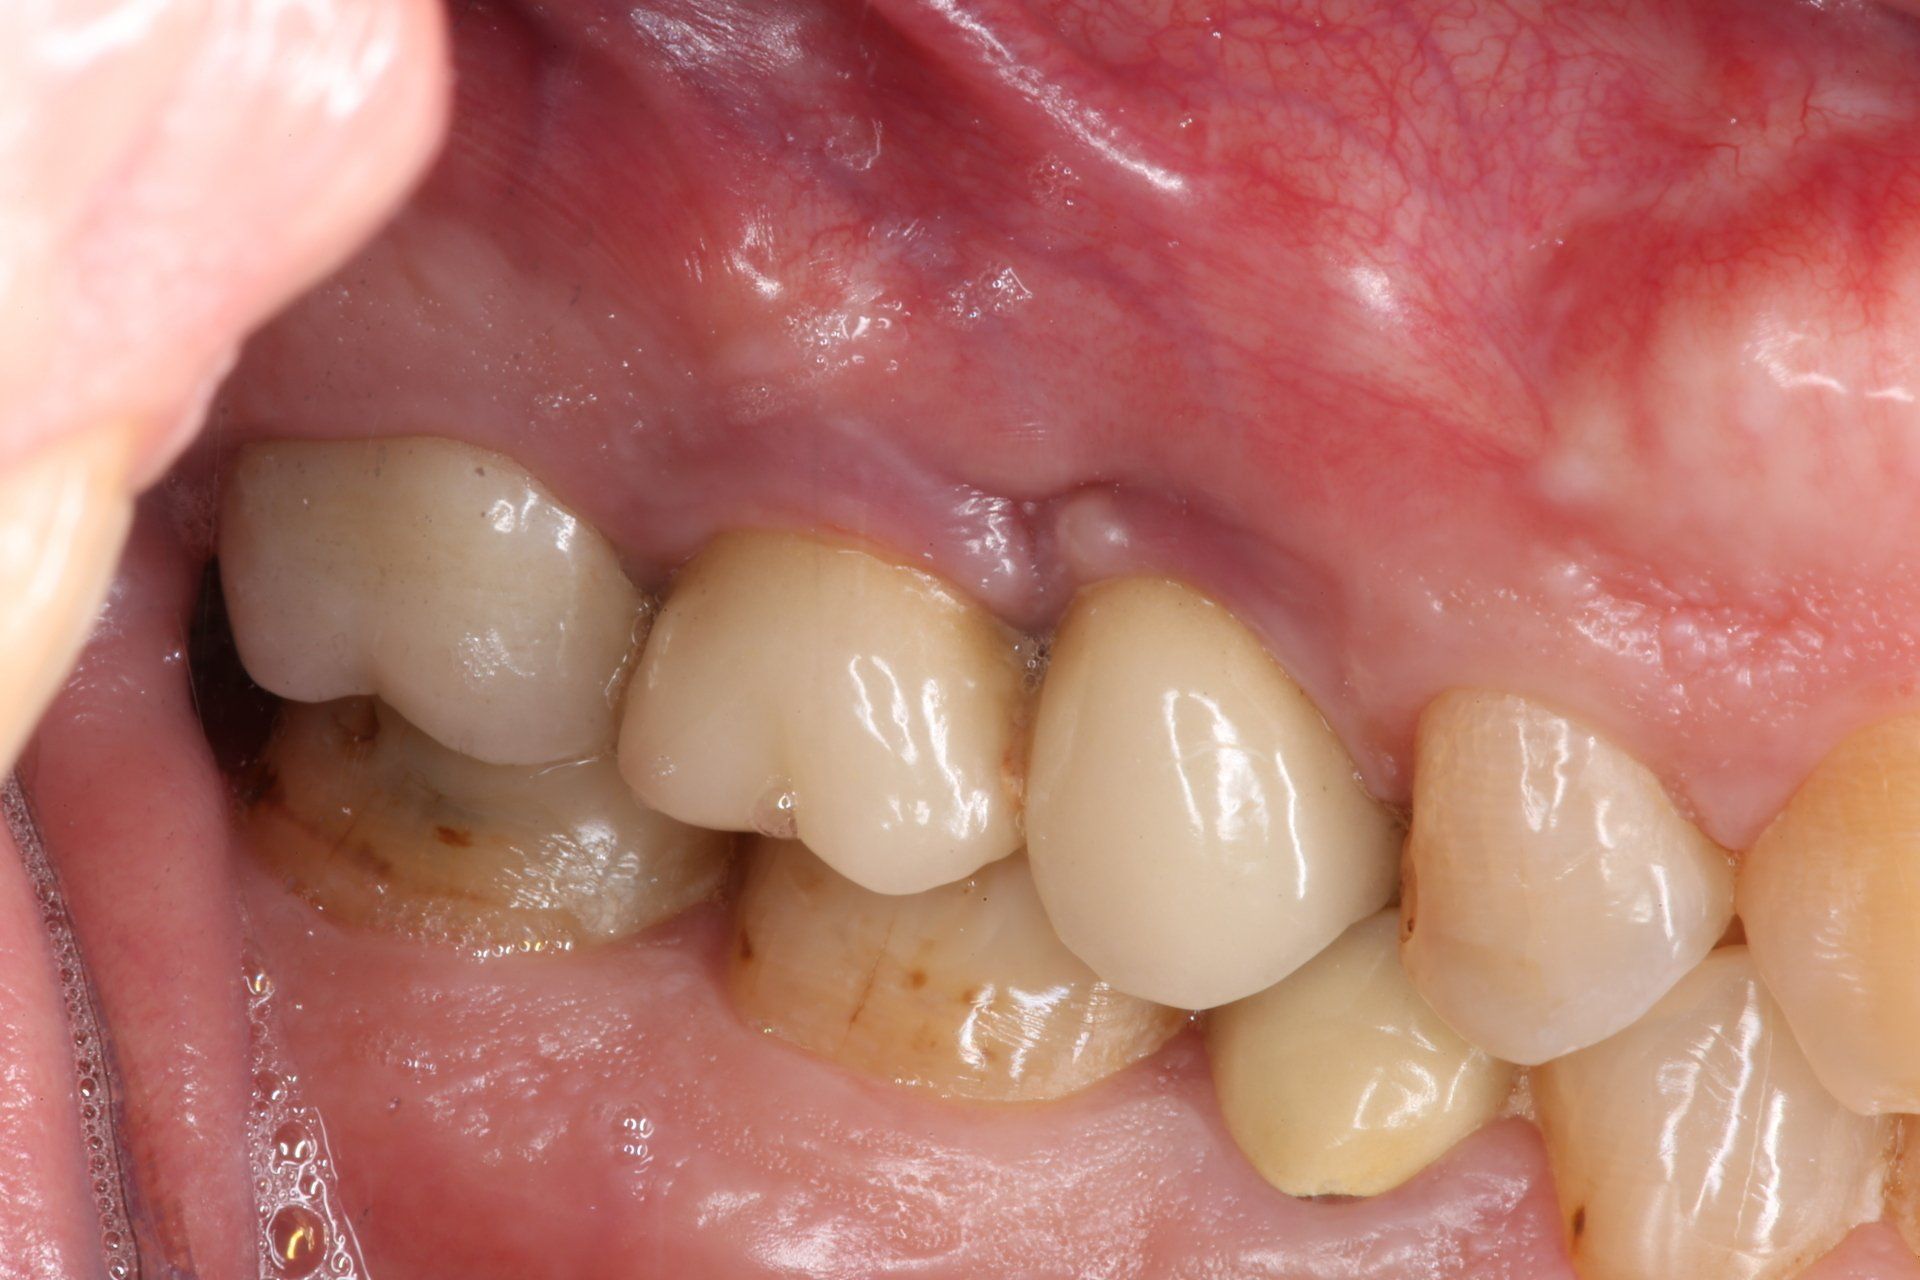

Dopo dieci giorni (T1) di utilizzo di PerioTabs®, si è notato un miglioramento dal punto di vista clinico (Fig. 8 e 9). Il P.I. è sceso al 57%, il BoP al 26% e sono diminuite anche le profondità di sondaggio (Fig. 10).

#dida Fig. 9.1 e 9.2: Foto laterale zona 2.5-2.6 a T1 prima e dopo il sondaggio

Il risultato estetico e l’aspetto clinico della salute tissutale è evidente a T2 (Fig. 11 e 12). Da notare un ulteriore miglioramento del P.I. sceso al 12% e del BoP diminuito al 2% (Fig. 13) dopo un'aggiuntiva istruzione e motivazione all’igiene orale domiciliare con l’uso dello spazzolino.

#dida Fig. 12: Foto dettaglio zona 2.5 e 2.6 a T2